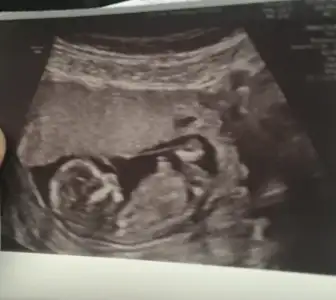

Ikra meyra Ikra meyra son kez kez yorumlaya bılır mısın canım. Zaten 13 hafta içindeyiz sonrası olmuyor herhalde en aşktaki şey nub oluyor herhalde

Eklentiler

• 48636F0E-9E4A-4C6B-B213-30C2A251402A.webp

48636F0E-9E4A-4C6B-B213-30C2A251402A.webp

23,1 KB · Görüntüleme: 146